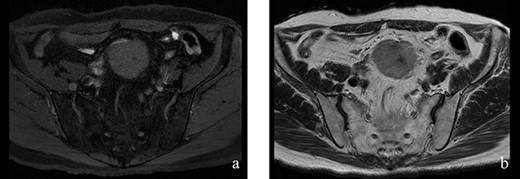

Figure 2: (a, b) The tumor had hypointensity on the T1-weighted images and mild hyperintensity on the T2-weighted images.